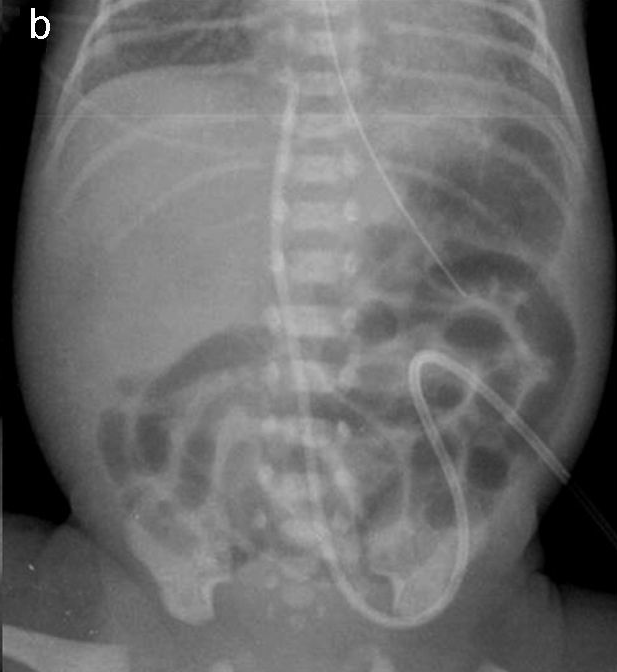

En neonatos, la obstrucción intestinal puede ser diagnosticada mediante una serie de hallazgos radiológicos característicos. La evaluación radiológica es crucial para diferenciar entre las diversas causas de obstrucción intestinal, que pueden ser de origen alto o bajo, y para determinar el manejo adecuado.

1. Radiografía Abdominal: Es la primera línea de imagen utilizada para evaluar la obstrucción intestinal en neonatos. Los hallazgos típicos incluyen dilatación de asas intestinales y la presencia o ausencia de niveles hidroaéreos, lo cual puede indicar si la obstrucción es proximal o distal. Por ejemplo, la «burbuja única» se asocia con atresia esofágica, la «doble burbuja» con atresia duodenal, y la «triple burbuja» con atresia yeyunal.[1-2]

2. Estudios de Contraste Gastrointestinal: Estos estudios son útiles para confirmar el diagnóstico y determinar la ubicación exacta de la obstrucción. Un enema de contraste puede mostrar un microcolon en casos de atresia ileal o colónica, y es particularmente útil para diagnosticar íleo meconial y enfermedad de Hirschsprung, donde se puede observar una zona de transición en el colon.[3-4]